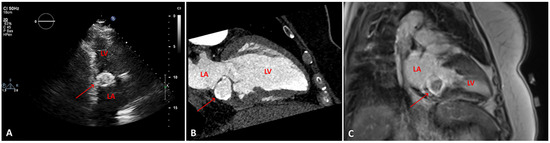

Figure 1.

A. transthoracic echocardiogram, two-chamber view showing a posterior mitral annulus caseous calcification (arrow), which appears as a well-defined brightened edge corresponding to an echodense periphery, and a central echolucent area corresponding to the central liquefaction. B. Computed tomography scan, showing a well-defined oval or crescent-shaped hyperdense mass with peripheral calcification (arrow). C. Late gadolinium enhancement-magnetic resonance imaging sequence, showing caseous calcification of the mitral annulus as a hypointense zone without late gadolinium enhancement (arrow). LV: left ventricle; LA: left atrium

A routine transthoracic echocardiogram (TTE) performed 4 years previously, with a view to orthopaedic surgery, had revealed a cardiac mass attached to the posterior mitral annulus with a mitral mean gradient of 6 mm Hg (at a heart rate of 80 beats per minute). At that time cardiac magnetic resonance imaging (cMRI) and computed tomography (CT) were performed and the diagnosis of caseous calcification of the mitral annulus was established (

Figure 1). Two years after the initial diagnosis, the patient developed third degree atrioventricular block for which a dual-chamber pacemaker was implanted. The patient was asymptomatic for a further 2 years until she developed an episode of acute severe dyspnoea.